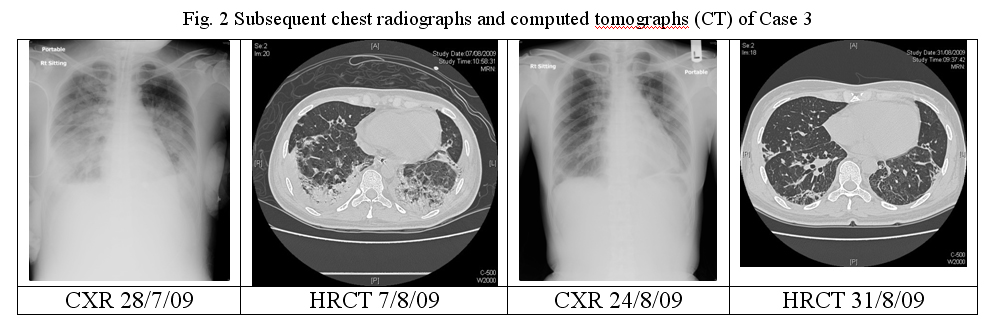

During her ICU stay, she required a long period of high PEEP of up to 28cmH2O for around 12 days while she was on mechanical ventilation. She had MRSA and Acinetobacter infections, with Vancomycin and Ciprofloxacin being prescribed. There was also the development of acute coronary syndrome, as evidenced by new T wave inversion over anterior leads and raised troponin I. Echocardiogram showed impaired left ventricular contraction with an ejection fraction (EF) of 40% only, together with hypokinesia over anteroseptal and apical segments of left ventricle. Aspirin was started. Improvement of left ventricular function (EF 71%) was observed in the follow-up echocardiogram on 24/8/09. Enoxaparin had been given for 10 days for prophylaxis of thromboembolism. Fortunately, her condition improved and she was able to come off ventilator support. The total duration of mechanical ventilation and ICU stay were 23 and 33 days respectively. She received further rehabilitation in general ward with much improvement. On Day 45 of admission, she was discharged home. She was able to walk unaided with no shortness of breath. CXR before discharge showed residual fibrosis mainly over both lower zone and HRCT thorax on Day 49 showed ground glass attenuation, streaky shadows and small cystic areas in both lung fields compatible with residual fibrosis & bronchiectasis due to previous inflammation. (Fig.2)